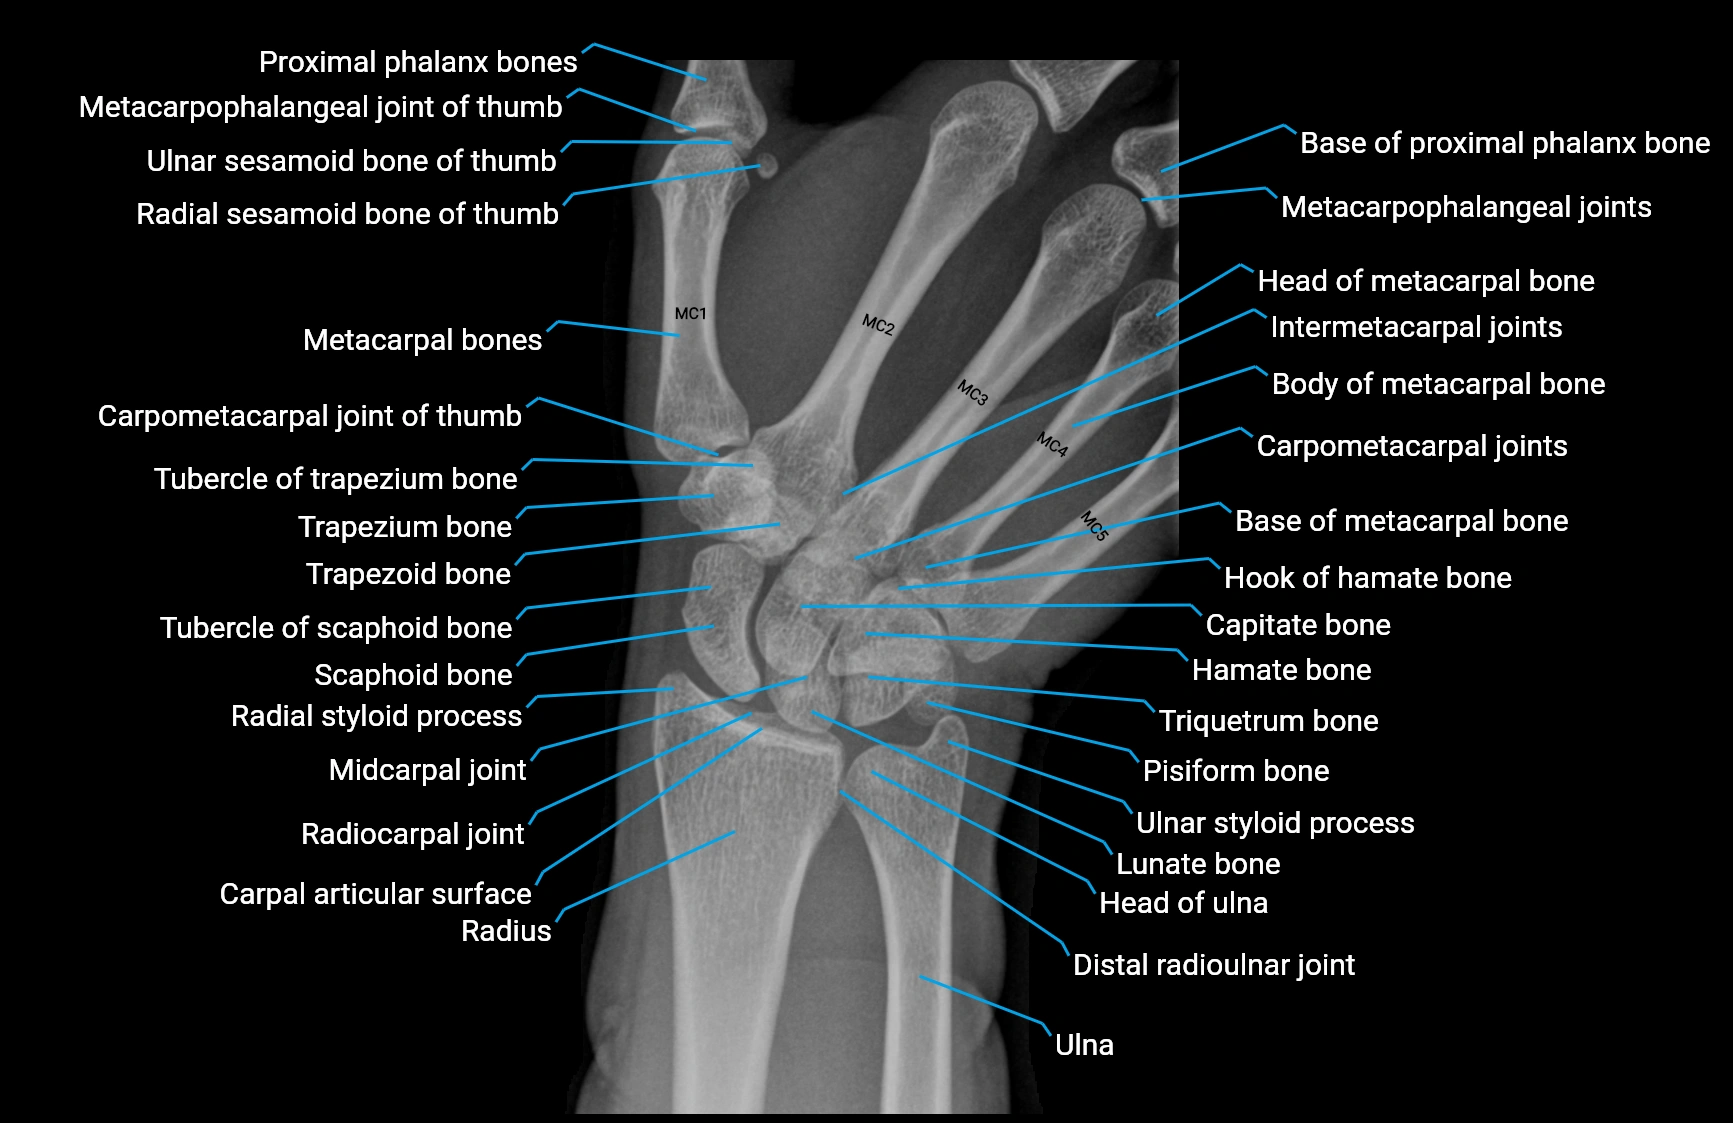

CT Appearance

Non-Contrast CT:

• Muscle: soft-tissue density, well defined in the hypothenar region.

• Tendon: linear low-density structure extending to the base of the little finger.

• Calcification or chronic scarring may appear as localized high-density foci.

• Useful for assessing bony attachment sites at the pisiform and proximal phalanx.